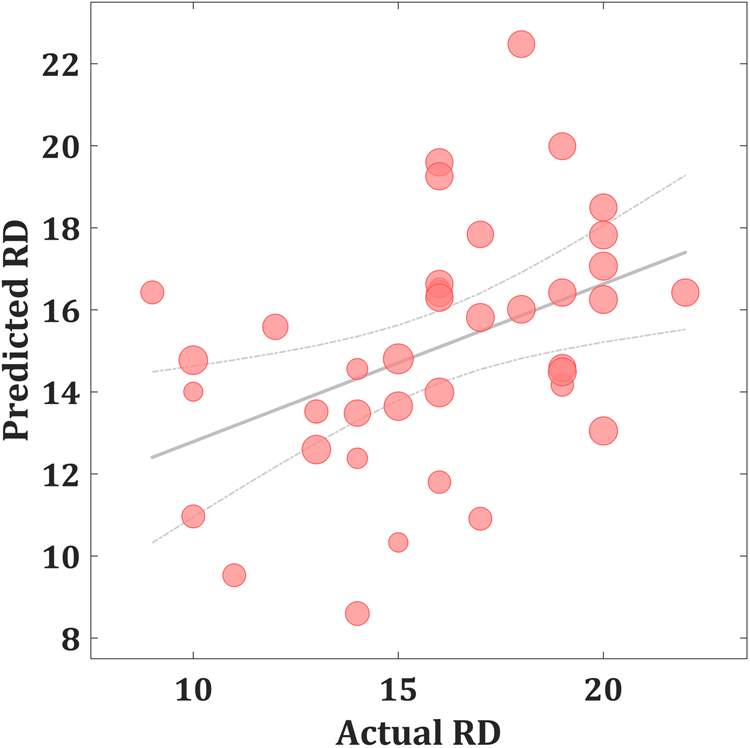

As shown in Fig. 1, the predicted RD scores significantly correlated with the actual RD scores (r = 0.425, p = 0.004; rMSE = 3.418, p = 0.015). Contributing to the predictions of RD, the MKL regression identified metabolic activity in the pontine nuclei (PO) and LC, the medial reticular formation (MRF), the dorsal/median raphe nuclei, the VTA, red nucleus, and substantia nigra [Fig. 2, only those voxels that survived at CV procedure are reported, the spatial location is identified by AAL3 (Rolls, Huang, Lin, Feng, & Joliot, Reference Rolls, Huang, Lin, Feng and Joliot2020) and the Harvard Ascending Arousal Network Atlas (Edlow et al., Reference Edlow, Takahashi, Wu, Benner, Dai, Bu and Folkerth2012)]. In addition, the age, gender, and mean global CMRglc value also contribute to MKL prediction (4.64% of total weight). The voxel-wise correlations indicated that the metabolic activity in these regions was positively correlated with RD scores. In addition, brain stem CMRglc was not predictive for HA (r = 0.164, p = 0.115; rMSE = 8.34, p = 0.152) and NS (r = −0.122, p = 0.516; rMSE = 6.26, p = 0.533) scores.

Fig. 1. Scatter plot showing actual and predicted reward dependence (RD) scores (r = 0.425, p = 0.004; rMSE = 3.418, p = 0.015). The size of scatter point is proportional to the mean global CMRglc value.